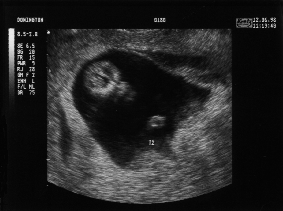

11 Weeks - Friday 12th June 1998 (Approx 50mm)

Eleven Week Scan 2

Top of Twin 2's (Lucy's) head with right hand in middle of shot.